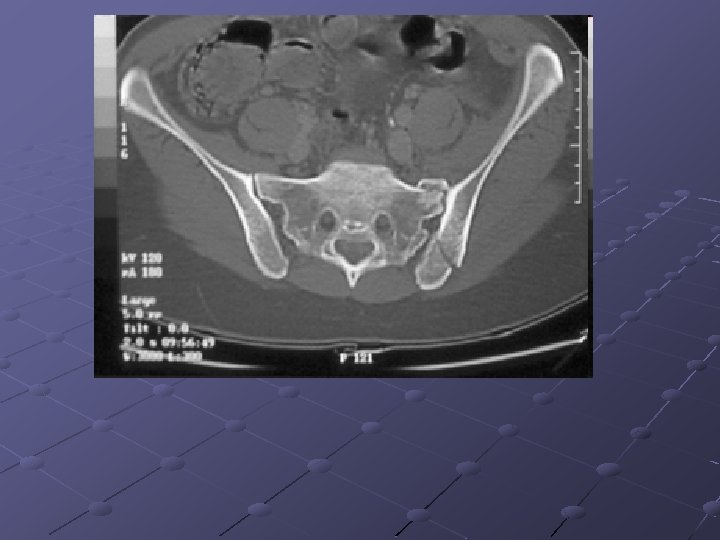

Imaging Studies